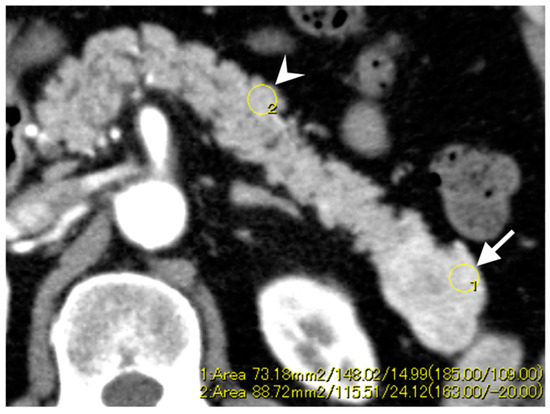

3.3. Enhancement Patterns of Pan-NENs Related to Low or High PAX6 Expression

| Calcification | 4 | 4 | 0.92 | 0.055 |

| Enhancement ratio c | ||||

| Arterial phase | 1.19 ± 0.44 | 1.38 ± 0.36 | 0.28 | |

| Portal phase | 1.12 ± 0.28 | 1.30 ± 0.22 | 0.044 |